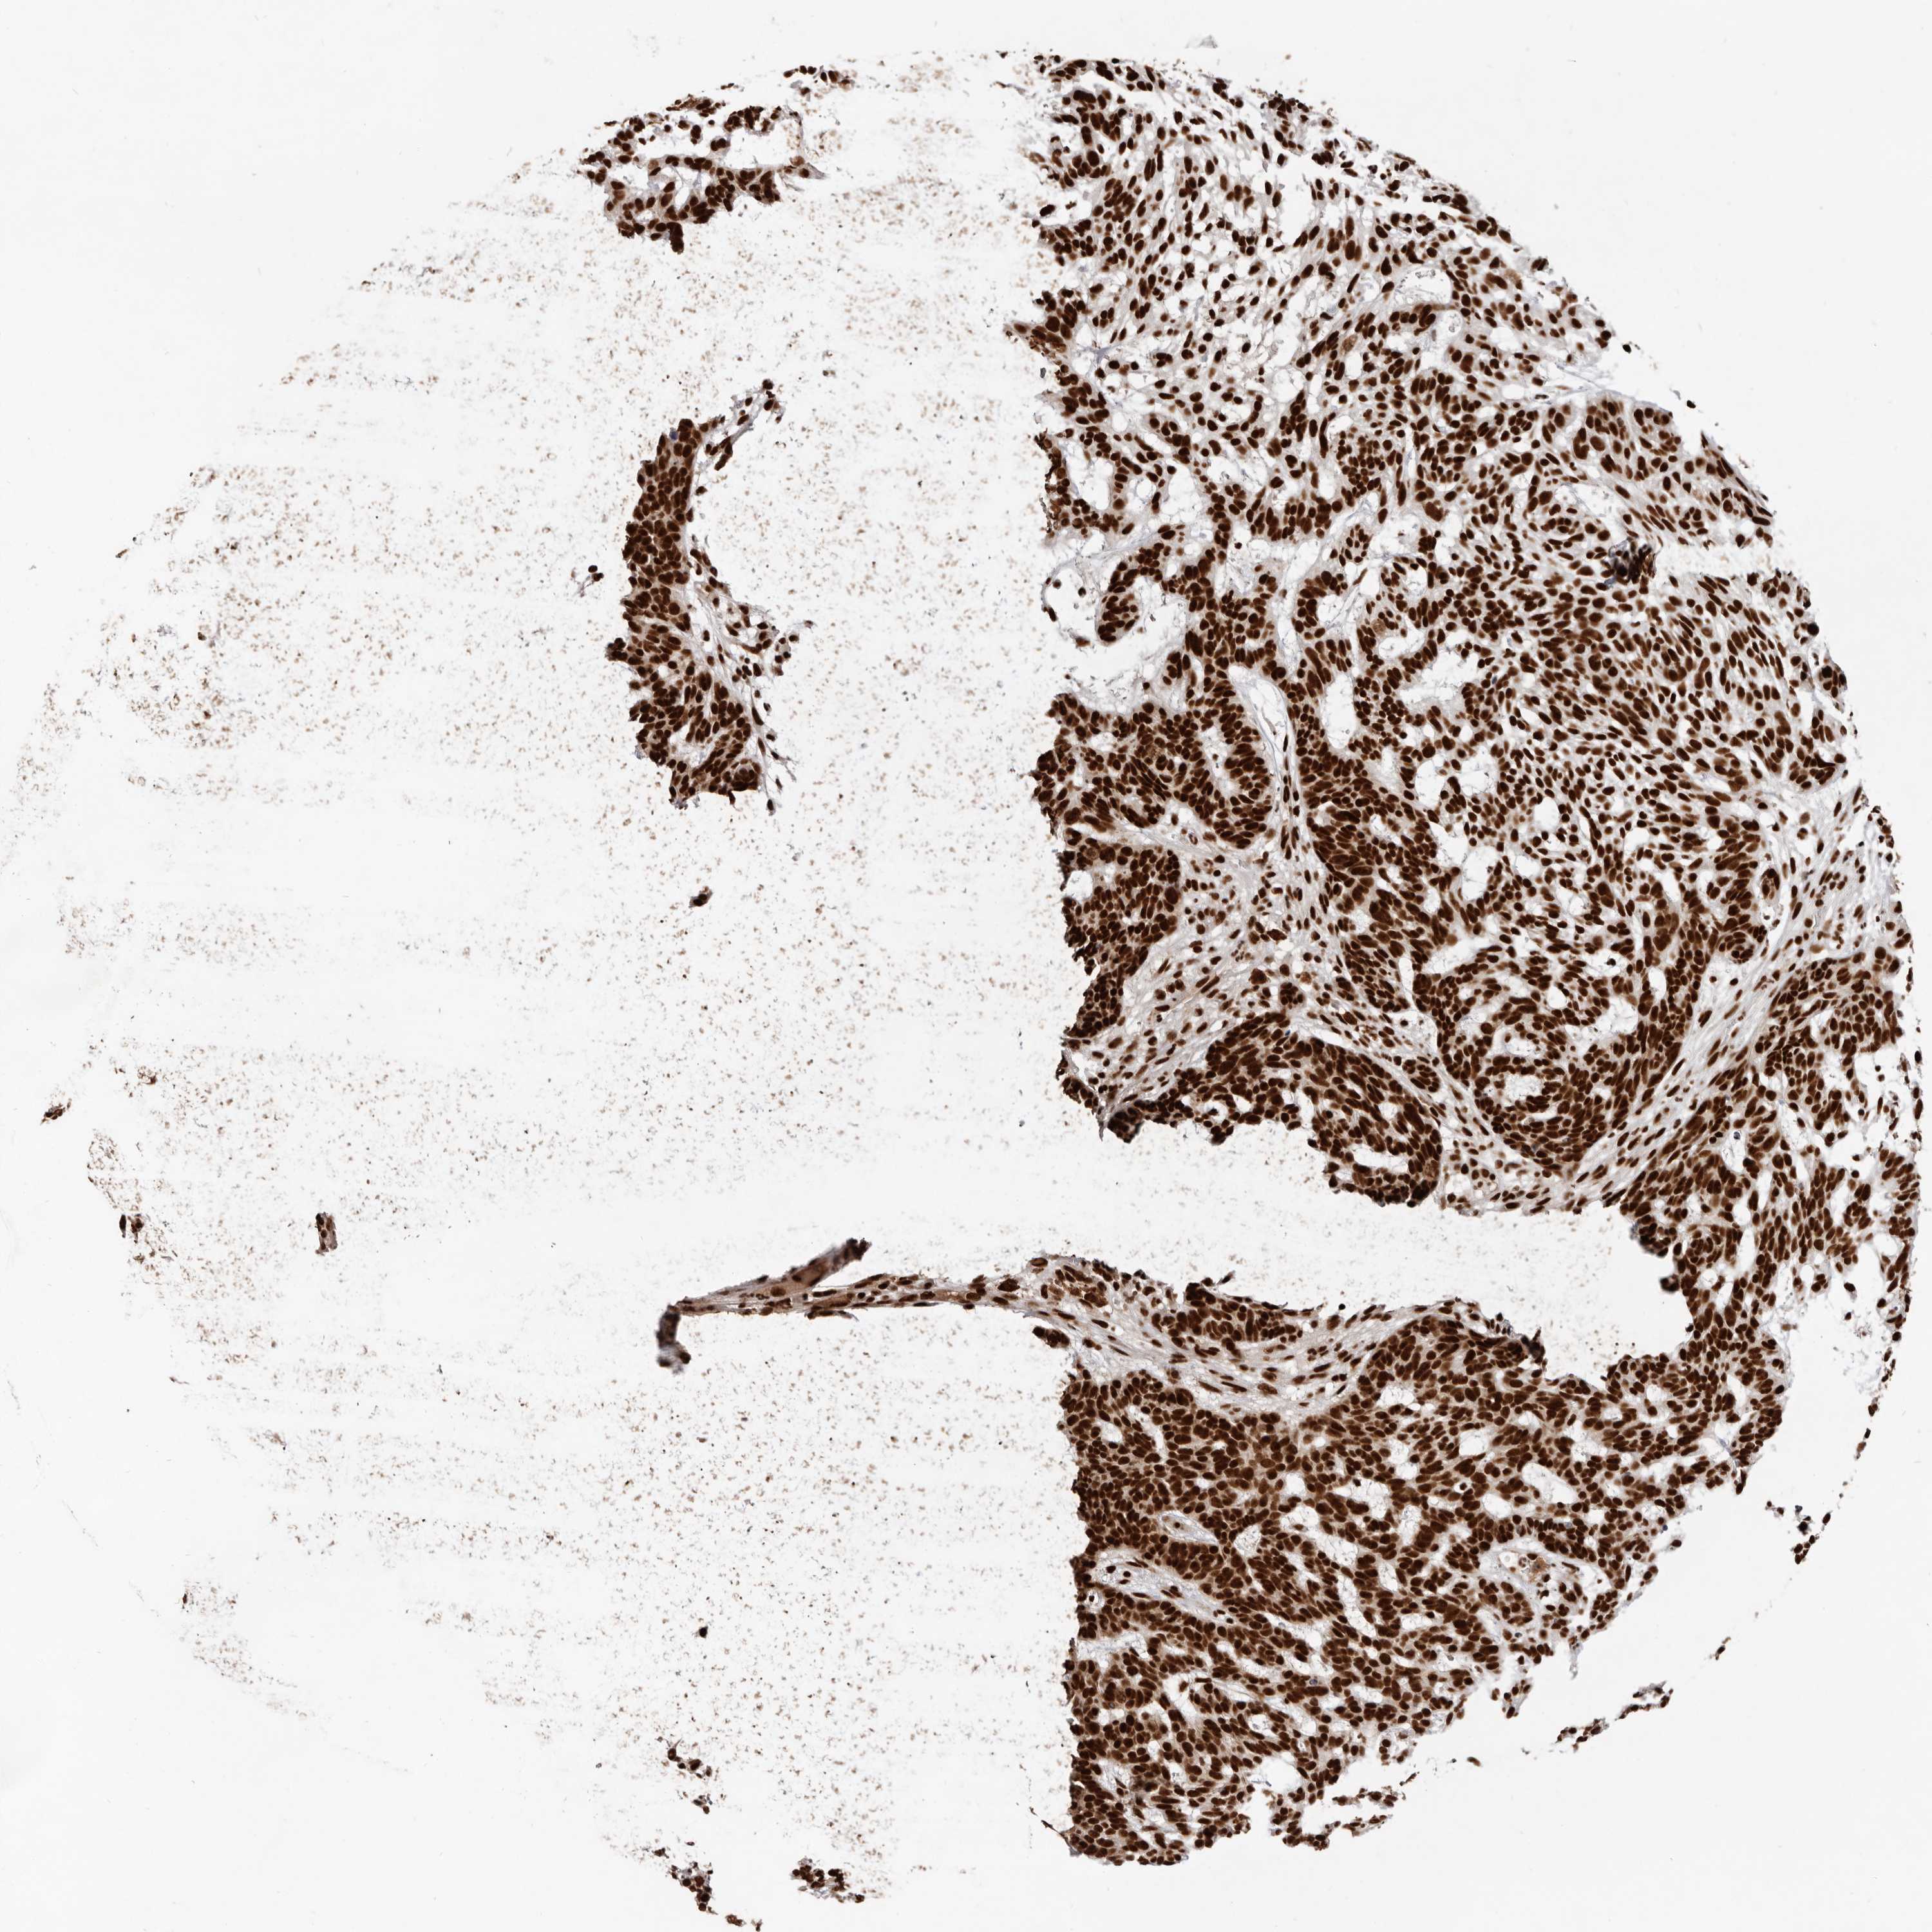

Antibody HPA028647

Staining

High

Intensity

Strong

Quantity

>75%

Location

Nuclear

Squamous cell carcinoma, metastatic, NOS

Squamous cell carcinoma, NOS